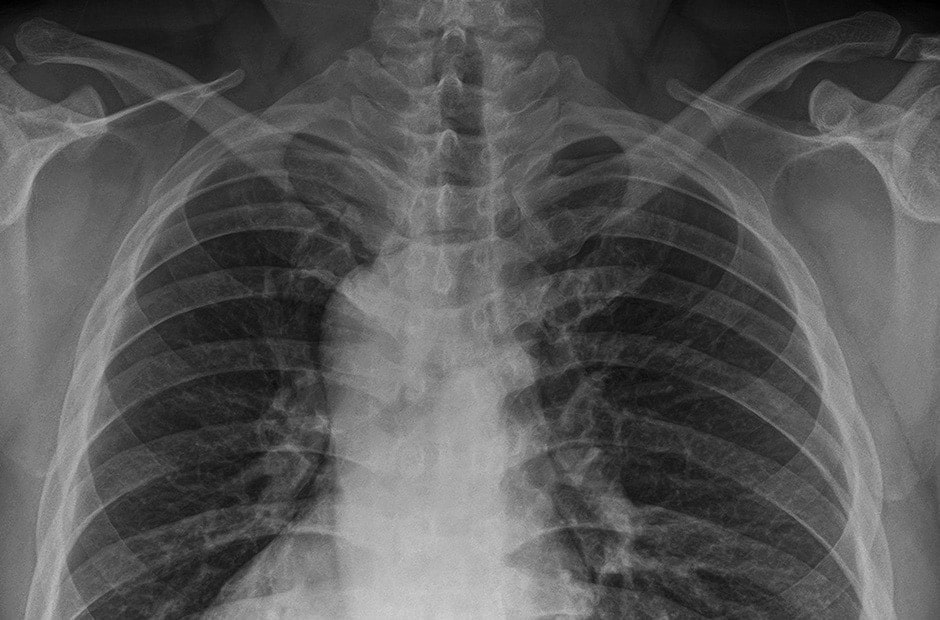

Klare Bilder erhalten